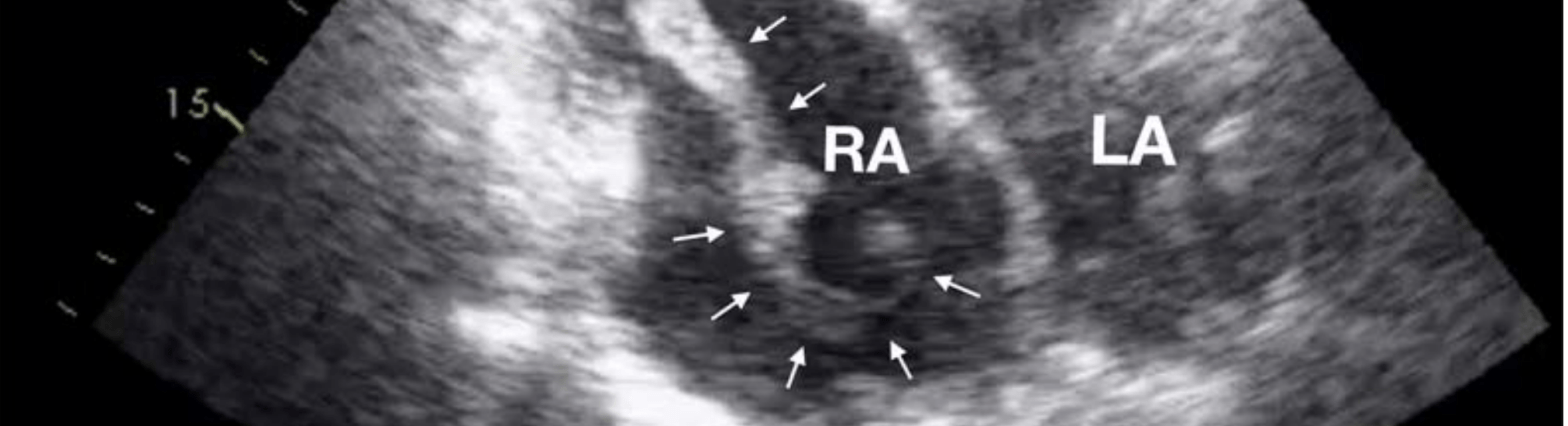

More contemporary echo studies similarly show that the RA is a site of thrombus formation.

One example is the consistent finding of elevated levels of fibrinogen and d-dimer in those with AF. This has been seen repeatedly. In fact, the spontaneous echo contrast we see on imaging is partly due to RBC aggregation. And, of course, fibrinogen promotes the aggregation of RBCs. Similarly, markers of endothelial injury, including vWF, are elevated in patients with AF.

But, even accounting for this, PE is far less common than systemic embolization. Most commonly, stroke. One reason stems from the appearance of the right atrial appendage. Not only does the right atrium have an appendage, just as with the LA appendage, it is the most common site of thrombus formation. But it is also quite different in appearance compared to the left atrial appendage. It is broader and more shallow and lacks recesses. This, along with some other differences, likely contribute to the lower rates of RA thrombus.

Image credit: Cresti A, García-Fernández MA, Miracapillo G, et al. Frequency and Significance of Right Atrial Appendage Thrombi in Patients with Persistent Atrial Fibrillation or Atrial Flutter. Journal of the American Society of Echocardiography. 2014;27(11):1200-1207.